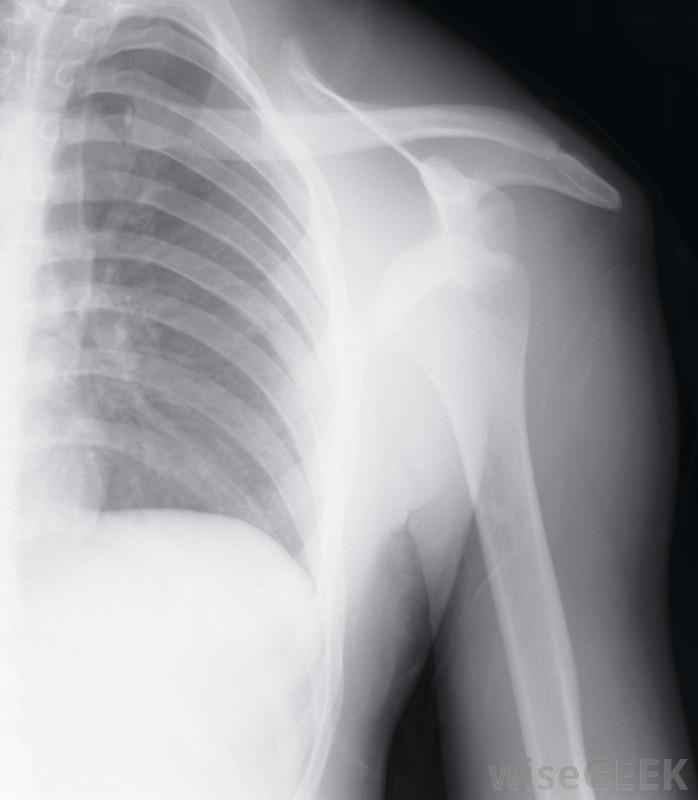

肩峰成形術是一種外科手術,治療因撞擊綜合征引起的肩部疼痛和虛弱。肌腱穿過肩胛骨頂部的肩峰骨下方,如果這些肌腱受傷或發炎,他們可以摩擦肩峰下側。肩峰成形術的目的是平滑或去除肩峰的任何粗糙部分,以便為肌腱創造更多的活動空間。在進行肩峰成形術之前,外科醫生可能需要做X光透視來觀察肩關節的骨骼。運動員如果參加包括手臂和肩部頭頂運動的體育活動,可能會患上撞擊綜合征肩部肌腱,尤其是肩袖,也可能是由于過度使用或重復性活動,如繪畫或提舉引起的。如果患者出現持續性疼痛,但用消炎藥、休息或冰敷都無法緩解,外科醫生可能需要進行肩峰成形術如果患者出現持續性肩痛,他的外科醫生可能想做一個肩峰成形術,他可能會先安排一系列的x光片來觀察肩關節的骨骼。其他的檢查,如核磁共振成像(MRI),也可能會被要求提供肩部有液體如果外科醫生認為肩峰成形術對患者有利,則可將其作為開放手術或關節鏡手術進行。如果冰敷和休息不能治療肩關節疼痛,肩峰成形術可能是必要的。開放性肩峰成形術是在肩前部切開一個切口,以使肌腱和肌肉都能看到。外科醫生可以切除肩峰骨的前部把骨頭下面的脊線剃掉,使其表面光滑。然后在切口打開時評估活動范圍。這種開放式手術可能需要更長的恢復時間,但它使外科醫生有更多的機會接觸肩部區域醫生可能會建議對肩關節疼痛和虛弱的患者進行肩峰成形術。肩峰成形術也可以作為一種關節鏡手術進行,其中一些在肩關節區域進行切口。插入關節鏡(包含攝像機和光源)以查看肩峰和肩關節。還插入手術器械來刮除或移除部分肩峰。這種關節鏡手術創傷小,恢復時間短在肩峰成形術后,病人應該在醫院呆上幾個小時到一個晚上。可能會有疼痛和腫脹,可以用冰和止痛藥治療。外科醫生也可以在手術后一兩天開始進行物理治療練習。通常情況下,對患者來說遵循外科醫生和理療師的建議,以使肩關節完全恢復活動范圍。開放性肩峰成形術比關節鏡手術更具侵入性。